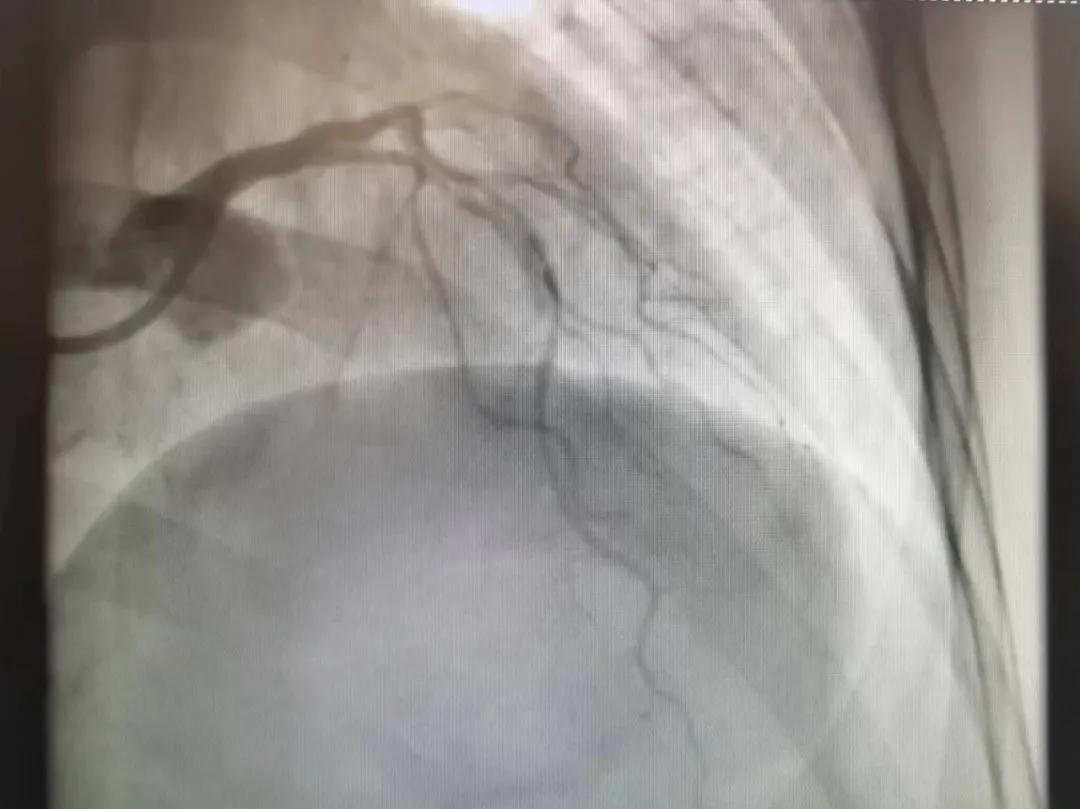

病人是位六十多歲的女性患者,有長期高血壓病史,1個月前開始出現(xiàn)胸悶胸痛,口服藥物治療效果不佳,經(jīng)朋友介紹,來到市二院心血管內(nèi)科。入院后完善冠狀動脈造影提示:前降支全程彌漫性狹窄伴鈣化,最重95%,回旋支狹窄約85%,右冠脈全程狹窄伴鈣化,最重60%。血管內(nèi)超聲顯示右冠脈開口面積3.36mm²,可見環(huán)形鈣化,考慮患者病變程度重、鈣化明顯,常規(guī)器械無法實現(xiàn)病變的良好預處理,且有很高的冠脈穿孔、血管夾層的風險。

術(shù)前